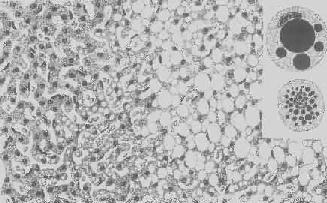

形态学:轻度肝脂肪变性时,肝肉眼观可无明显改变,或仅轻微黄染。如脂仿变性比较显著和广泛,则肝增大,色变黄,触之质如泥块并有油腻感。镜下,肝细胞内的脂肪空泡较小,起初多见于核的周围,以后变大,较密集散布于整个胞浆中,严重时可融合为一个大空泡,将细胞核挤向胞膜下,状似脂肪细胞(图1-18)。脂肪变性在肝小叶中的分布与其病因有一定的关系,例如肝淤血时,小叶中央区缺氧较重,故脂肪变性首先在此处发生。但长期淤血后,小叶中央区的肝细胞大多萎缩、变性或消失,于是小叶周边区肝细胞也因缺氧而发生脂肪变性。磷中毒时,肝细胞脂肪变性则主要发生于小叶周边区,这可能是由于此区肝细胞对磷中毒更为敏感的缘故。

肝细胞脂肪变性

图1-18 肝细胞脂肪变性

肝细胞胞浆内出现大小不等的脂肪空泡;右上角为饿酸染色的脂肪细胞, 脂滴染成黑色